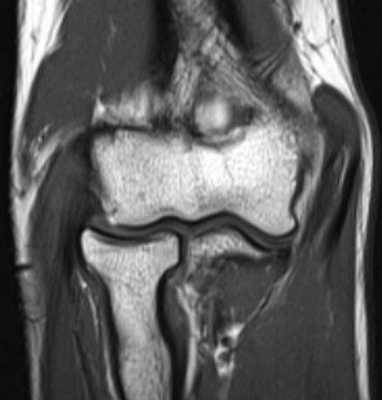

МРТ локтевого сустава в корональной плоскости. В подкожно-жировой клетчатке локтевого сустава отмечаются множественные образования неправильной вытянутой формы, местами сливающиеся между собой — вероятно, венозная мальформация.